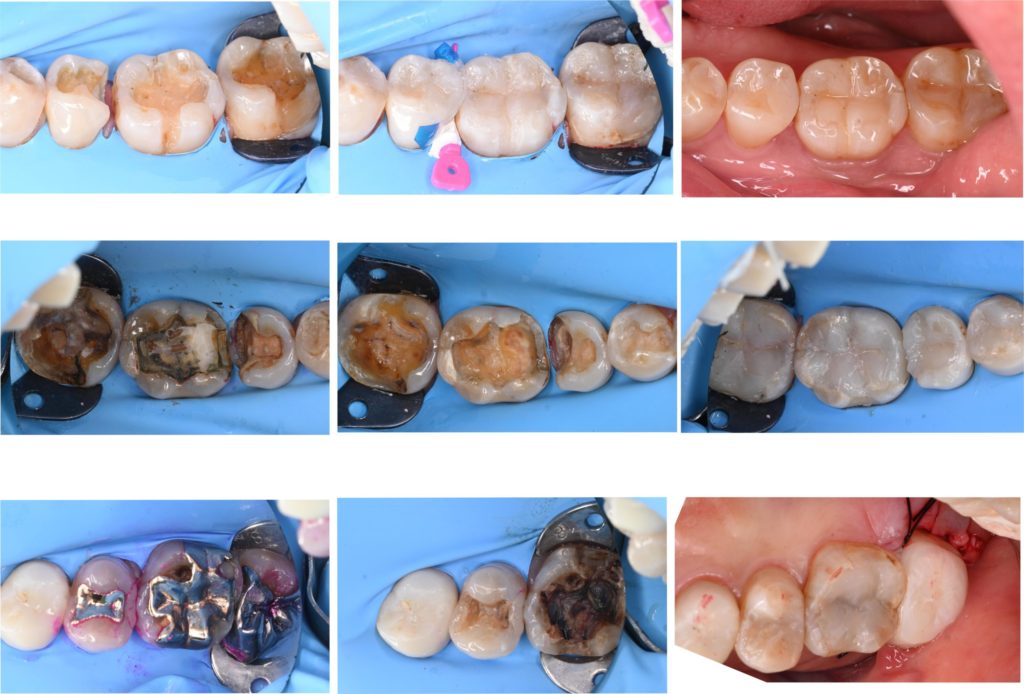

デジタルデータからのシミュレーションを行い、3Dプリンターから製作したモックアップ(歯を削る前材料を盛り足して確認してもらう作業)を行いました。歯を削る前に仕上がりの状態をお伝えすることが可能です。

モックアップの上からセラミックの厚みに必要な量を最小限削ります。エナメル質を温存することで、歯の強度の確保、接着の向上に有利に働きます。